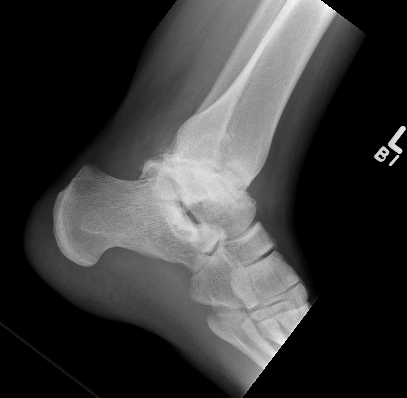

Talar AVN